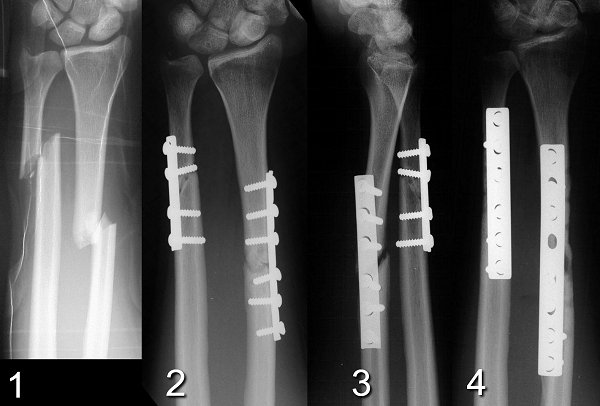

Изображения повреждения костей